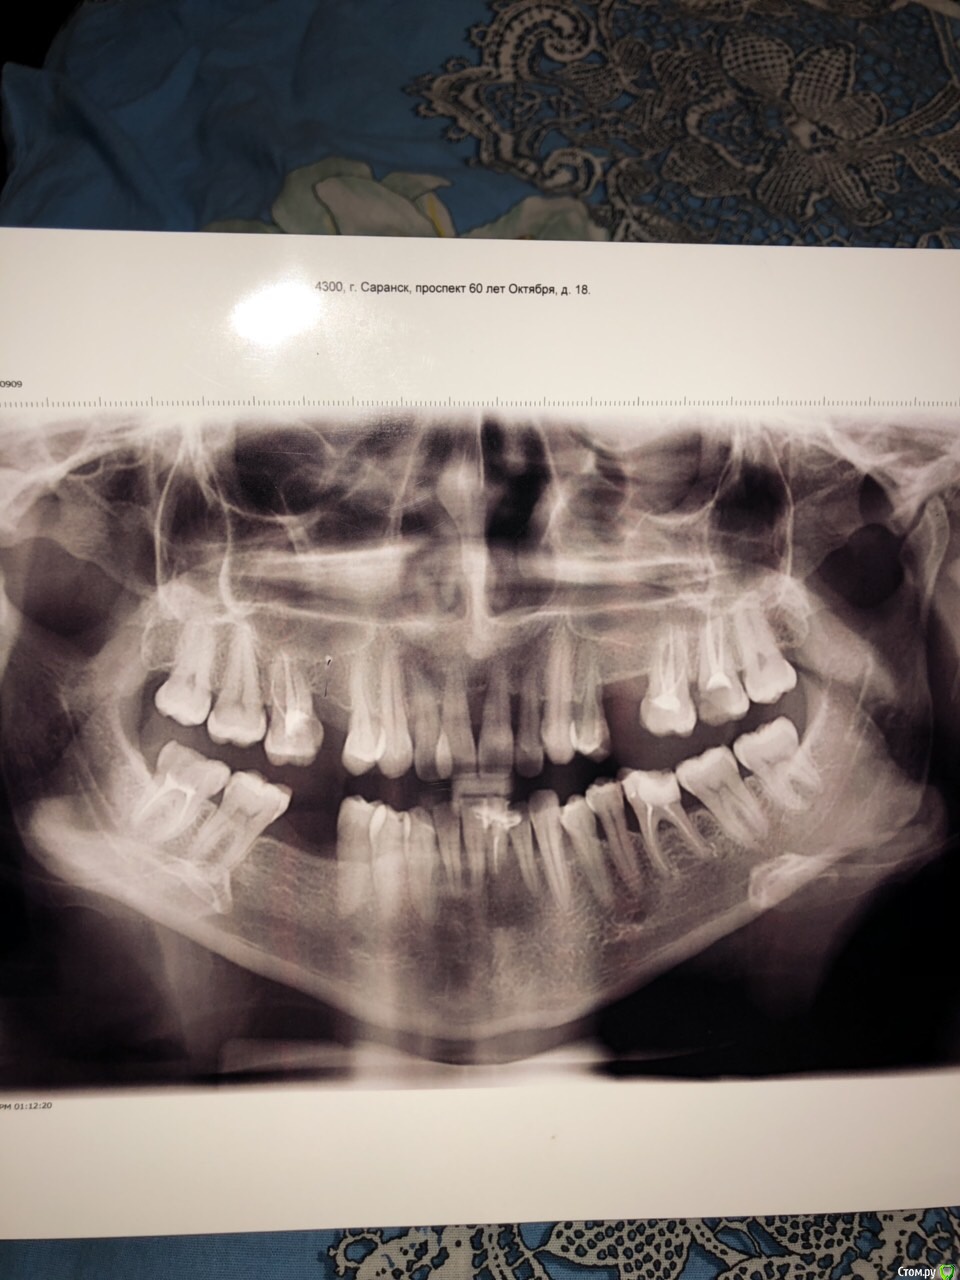

Марго88 Опубликовано 14 декабря, 2018 Поделиться Опубликовано 14 декабря, 2018 Здравствуйте , мне 30лет . Пародонтит у меня лет с 14 . Картина ужасная . Сейчас пытаюсь исправить ситуацию . Удалили нижние еденицы . Так совсем уже не держались, кость уходит совсем( врач назначил брекеты . Очень боюсь усугубить ситуацию. После брекетов хочет делать пластику мембраной и ставить имплантанты .спасибо . Ссылка на комментарий

Дмитрий Л. Опубликовано 15 декабря, 2018 Поделиться Опубликовано 15 декабря, 2018 Не торопитесь. Найдите врача, который знает значение слова кюретаж, лоскутная операция, подсадка десны и тд. Это пародонтит тяжелой степени и зубы подлежат удалению.Но медицина штука интересная. Я бы за фронтальные зубы поборолся. Типичный план лечения:шинировать зубы, почистить корни, обучить вас чистить зубы. Бросить курить. Ссылка на комментарий

Марго88 Опубликовано 15 декабря, 2018 Автор Поделиться Опубликовано 15 декабря, 2018 Не торопитесь. Найдите врача, который знает значение слова кюретаж, лоскутная операция, подсадка десны и тд. Это пародонтит тяжелой степени и зубы подлежат удалению.Но медицина штука интересная. Я бы за фронтальные зубы поборолся. Типичный план лечения:шинировать зубы, почистить корни, обучить вас чистить зубы.Бросить курить. Это все понятно ) я и написала что мне удалили нижние два зуба , там было сделано все что можно , но держаться уже не на чем . За фронтальные зубы мой врач тоже будет бороться . Хотела узнать брекеты в моем случае разрешены или нет ? Ссылка на комментарий

Марго88 Опубликовано 15 декабря, 2018 Автор Поделиться Опубликовано 15 декабря, 2018 Как мне объяснили надо выровнить рад , для того чтоб потом вставить имплантаты . Пока только работаем с нижней челюстью . Ссылка на комментарий